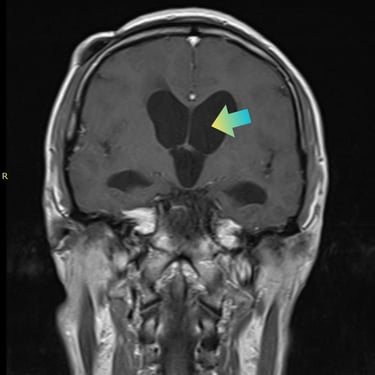

La hidrocefalia es una condición caracterizada por la acumulación anormal de líquido cefalorraquídeo en los ventrículos cerebrales, lo que genera aumento de la presión intracraneal y síntomas como cefalea, náuseas, alteraciones cognitivas y trastornos de la marcha. Cuando el manejo médico no es suficiente, la derivación ventriculoperitoneal (DVP) es el tratamiento quirúrgico más utilizado. Este procedimiento permite drenar el exceso de líquido desde el cerebro hacia la cavidad abdominal, donde es reabsorbido, aliviando la presión intracraneal y mejorando la función neurológica. El tratamiento oportuno es clave para prevenir secuelas.